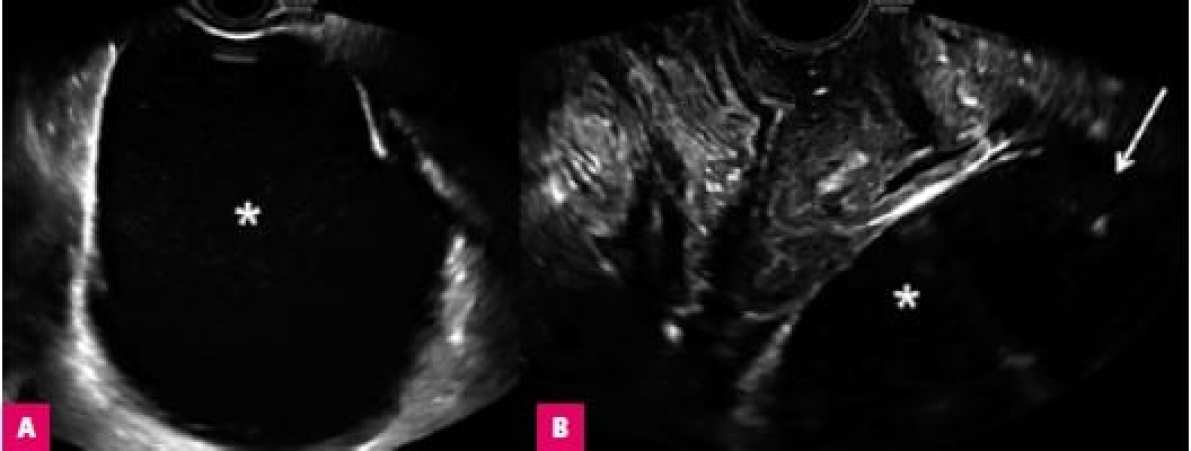

Ультразвук является широко доступным, неинвазивным и дешевым методом визуализации, который можно использовать без какого-либо риска для пациенток. Его преимущества также включают динамичность и интерактивность, предоставляя информацию о взаимном расположении брюшных и тазовых структур.

Для проведения УЗИ требуется высококачественный ультразвуковой аппарат с опцией высокочувствительного доплера, оснащенный головками высокого разрешения (5,0–9,0 МГц), а также трансабдоминальной конвекцией и линейными датчиками.

Благодаря возможности немедленной панорамной оценки брюшной полости и таза, УЗИ используется при диагностике возможных послеоперационных осложнений.

Трансвагинальное ультразвуковое исследование является наиболее широко доступным методом визуализации внутренних гениталий, а также смежных структур таза (например, мочевого пузыря, прямой кишки, сигмовидной кишки, тазовых и брюшных лимфатических узлов). Хотя этот метод можно считать золотым стандартом в предоперационной оценке аномалий матки и придатков, он не является тестом выбора в послеоперационной оценке. Не рекомендуется выполнять трансвагинальное УЗИ сразу после гистерэктомии из-за риска разрыва швов, а также из-за сложности диагностики кровоизлияния. Обследование должно проводиться опытным ультразвуковым врачом или гинекологом.

При обследовании трансабдоминальным методом из-за накопления кишечных газов (часто после операции) или высокого индекса массы тела может быть получение изображение низкого качества. Также на качество обследования выполненного в раннем послеоперационном периоде может повлиять дискомфорт пациентки, связанный с раневой болью.